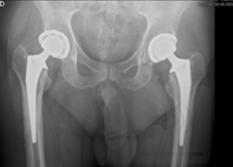

A Prótese da anca ou Artroplastia da anca, é uma das cirurgias mais gratificantes na cirurgia ortopédica contemporânea. Na atualidade, em Portugal, são efetuadas cerca de 15.000* próteses da anca por ano.

Na Unidade da Anca realizamos 500 próteses da anca anualmente.